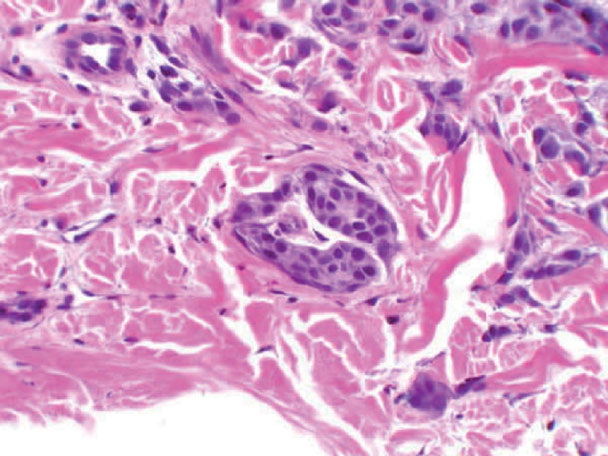

Skin Cancer and histopathology = سرطان الجلد